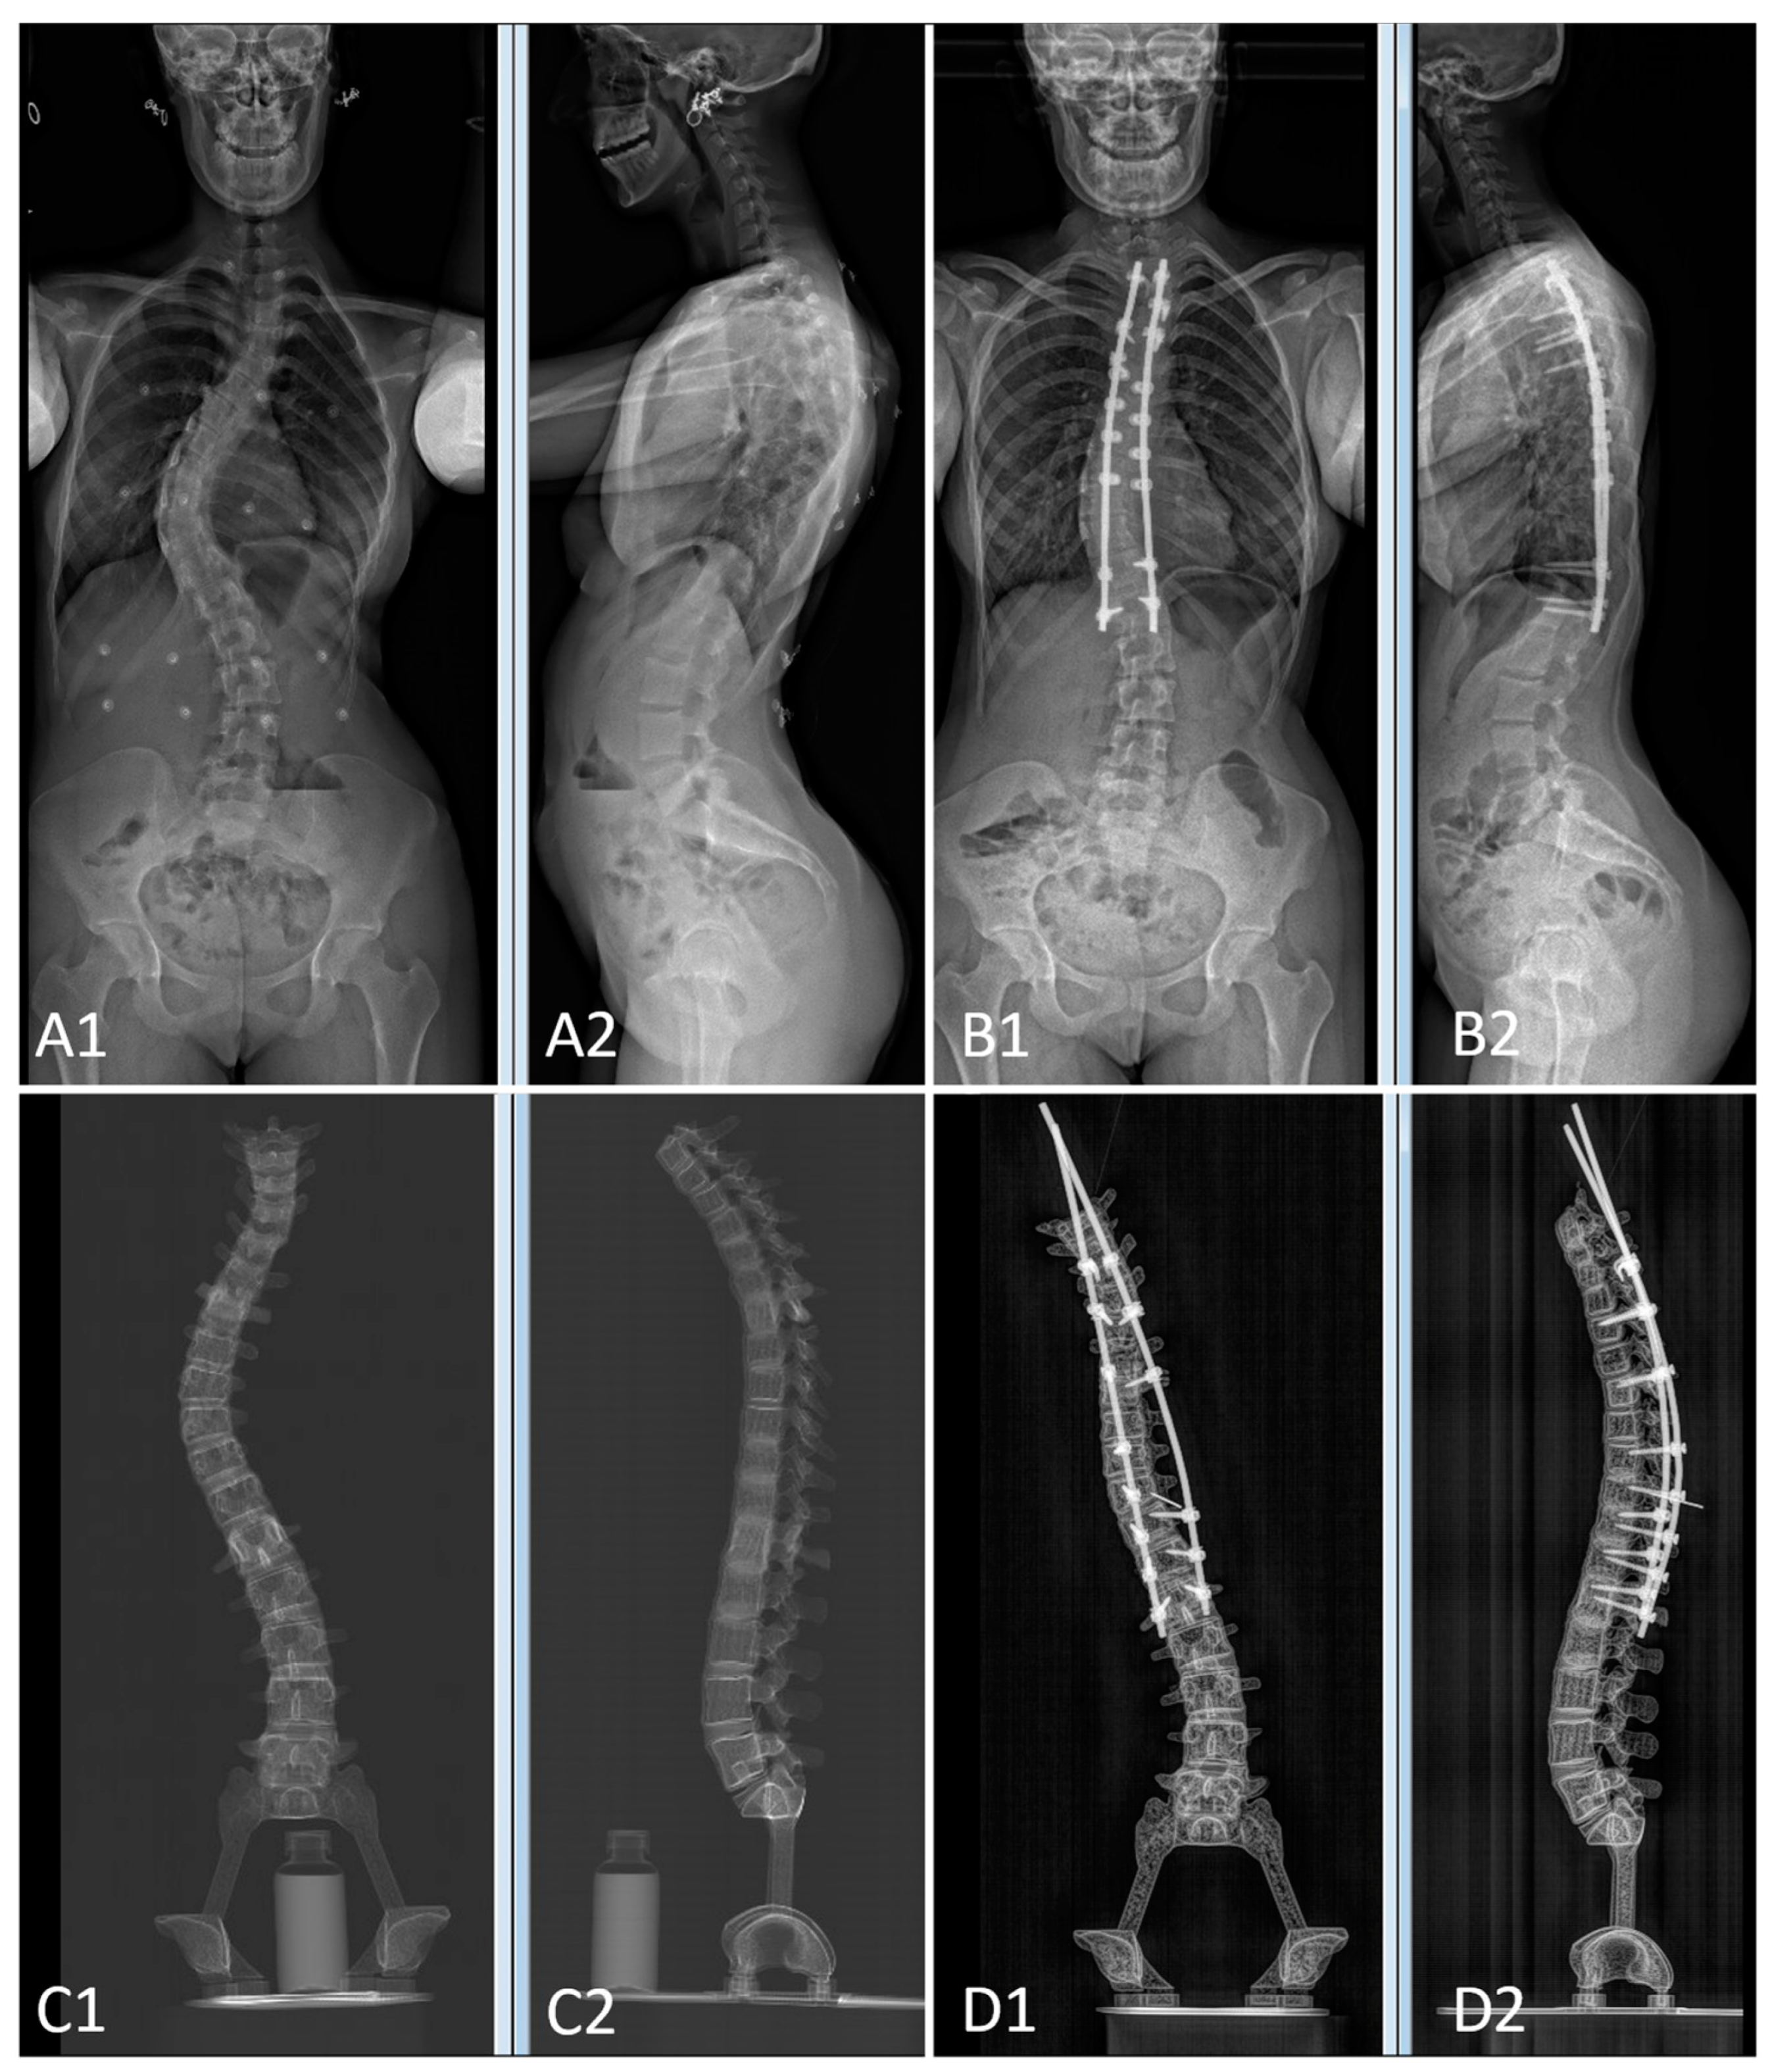

The pre- and postoperative constructs of one of the 3D-printed spine twins can be seen in Figure 9. Figure 8 (Patient 1) and Figure 10 (Patient 2) demonstrate pre- and postoperative bi-planar X-rays of the actual patient and their 3D-printed twin spine.

Figure 8. Bi-planar X-rays of patient 1 and 3D-printed twin 1. (A): Preoperative X-rays of patient 1 ((A1): frontal view, (A2): lateral view). (B): Postoperative X-rays of patient 1 ((B1): frontal view, (B2): lateral view). (C): Preoperative X-rays of 3D-printed twin 1 ((C1): frontal view, (C2): lateral view). (D): Postoperative X-rays of 3D-printed twin 1 ((D1): frontal view, (D2): lateral view).